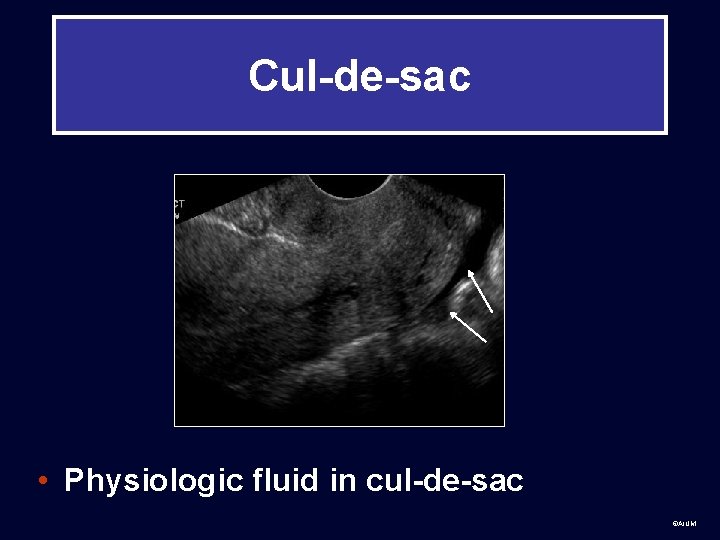

Cul-de-sac • Physiologic fluid in cul-de-sac ©AIUM